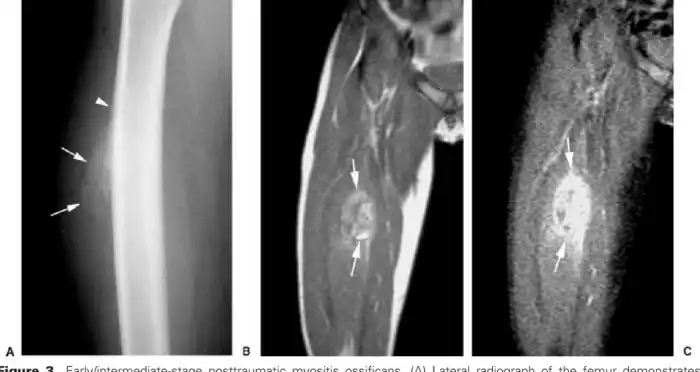

В первую очередь Юлиус пытается сравнить болезнь с Myositis ossificans circumscripta - схожим феноменом доброкачественных неопухолевых костных образований в мышцах и мягких тканях. Сегодня считается, что MОС, или оссифицирующий приобретенный миозит, имеет травматическую причину и более точное современное его название - myositis ossificans traumatica. Хотя механизм заболевания является загадкой, 80% появления «окаменелостей» в мышцах, преимущественно бедер и рук, являются последствием именно физической травмы. В отличии от фибродисплазии, эти камни единичны и не разрастаются так обширно. Хотя в некоторых случая межреберные пространства и грудные мышцы замещаются костной тканью в достаточно больших объемах. Возможно, вам это покажется отсылкой на суперспособности, когда после сильной травмы вы становитесь сильней, а ваши кости крепче. Что ваши ребра срастаются вместе, утолщаются за счет окостенения мышечной ткани и создают вам бронежилет, делающий вас неуязвимыми. Ну что же... это не так. Вообще, фраза о том, что сломанные кости становятся крепче, может звучать только от тех, кто их не ломал, а потом не сидел, обняв кота в свои 50 лет в дождливый вечер у окна. Реальность очень и очень далека от таких мифов, заключающихся в инвалидности, ограничении подвижности, проблемам с позвоночником и болями, в сравнении с которыми ваша межреберная невралгия даже рядом не стоит.

Костное образование в мышце на ноге:

Розентрин тоже не знал, почему так происходит. Единственная разница между нами и ним в том, что мы лучше знаем механизм образования костей и отличаем его от кальцинирования. Сегодня мы знаем, что при повреждении скелетной мышцы высвобождаются воспалительные цитокины - важные гормоноподобные белки. Эти белки, помимо иммунной системы, стимулируют эндотелиальные клетки кровеносных сосудов. Эндотелий в норме синтезирует множество веществ, регулируя огромный ворох функций - от артериального давления до проникновения воды, продуктов метаболизма в кровь и обратно - являясь не просто стенками вашей кровеносной системы, как полиэтиленовый пакетик, а живым регулятором, фильтром и средством контроля многих функций. Резкий выброс цитокинов заставляет клетки этого эндотелия превращаться в мезенхимальные стволовые клетки, что в большинстве случаев поможет вам восстановить повреждения. Но иногда что-то идет не так, и М.стволовые клетки дифференцируются на хондроциты и остеобласты. Остеобласты в организме формируют костную ткань, и если они появились, а все кости давно сформированы, они иногда могут начать формировать новую кость в том месте, где ей вовсе не место.